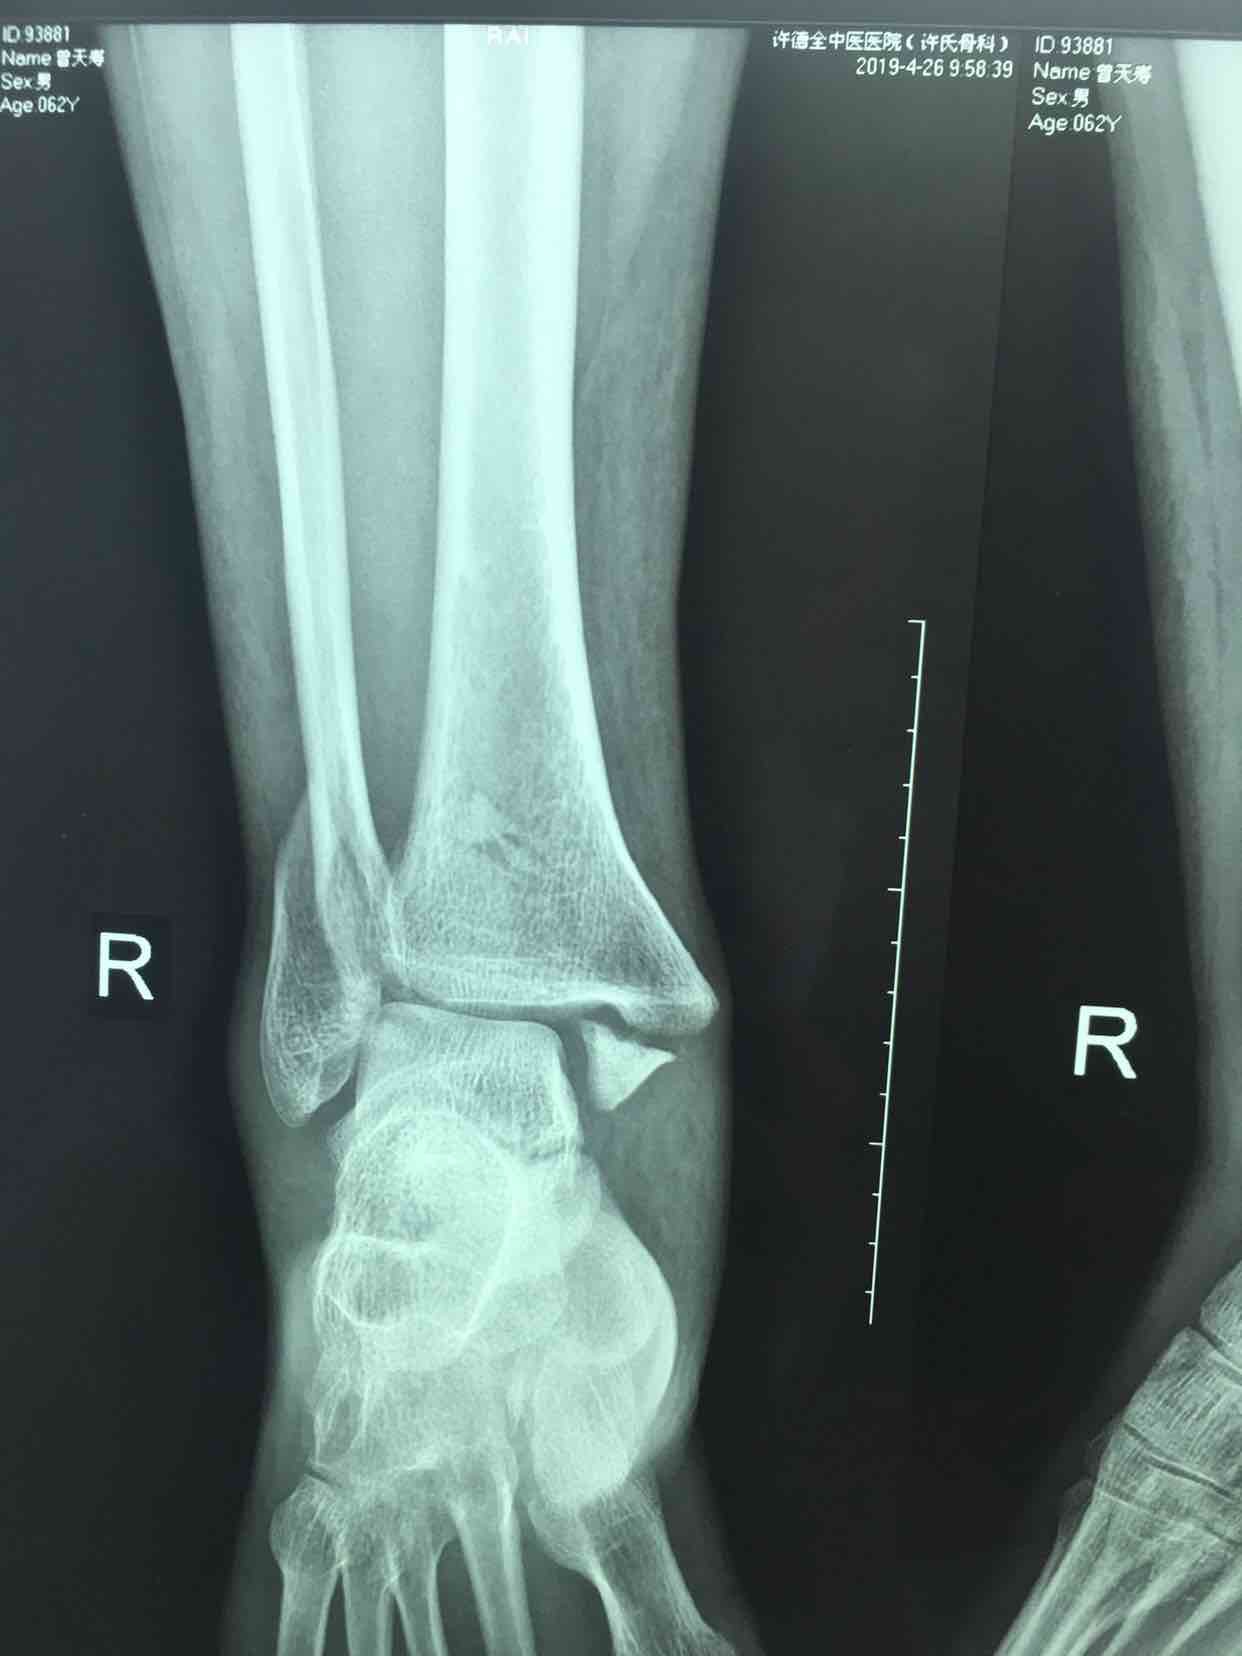

三踝骨折并胫距关节脱位(切复内固定术)

摔伤后右踝肿痛,畸形,活动受限1小时入院。既往身体健康,无特殊不良嗜好。

生命体征平稳,心肺复未见异常。右踝部肿胀,局部皮色发红,皮温高,畸形,压痛及纵叩痛阳性,可及骨擦音或骨擦感,踝关节活动受限,末梢血运感觉正常。

诊断三踝骨折并胫距关节脱位完善术前检查,待肿胀消退后在腰麻下行切复内固定术,术后石膏托固定,抗炎,消肿等处理。